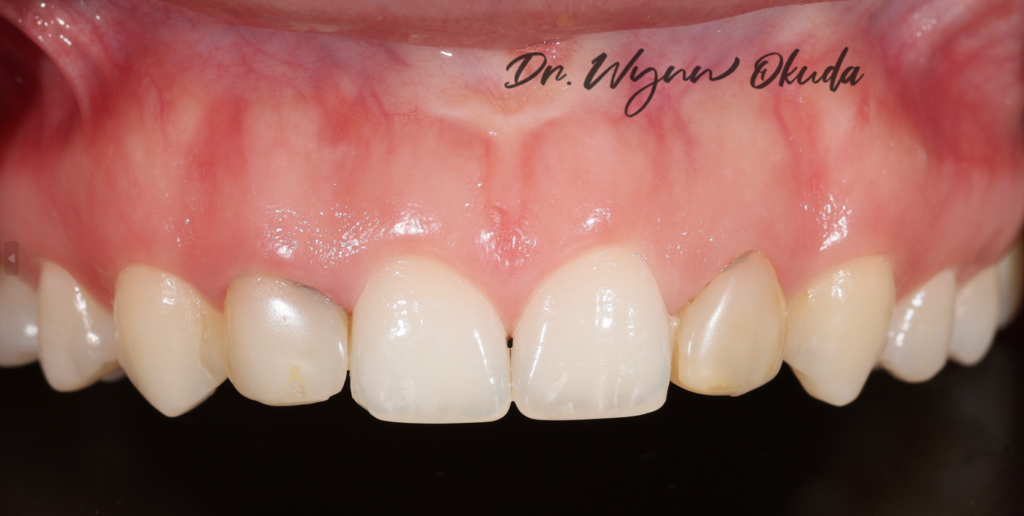

FIGURE 1 (BEFORE)

FIGURE 2 (AFTER)